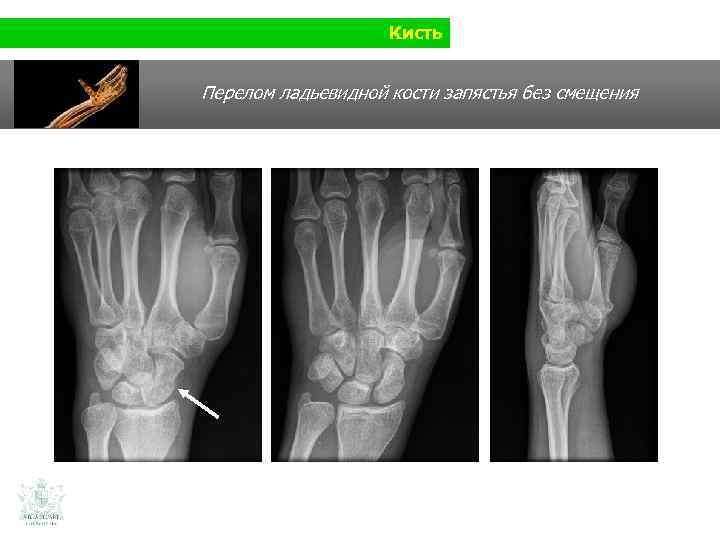

Кисть Перелом ладьевидной кости запястья без смещения

Кисть Перелом ладьевидной кости запястья без смещения Мини-инвазивный остеосинтез с канулярным винтом (Twin-Fix)